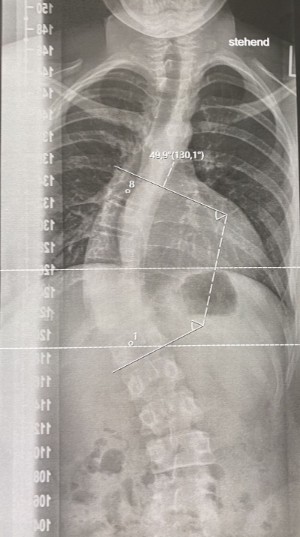

Imatge d’una placa de raigs X (imatge esquerra) amb una escoliosi de doble corba toràcica (a dalt) i contra-corba lumbar (a baix). A l’imatge dreta es pot veure l’esquena de la pacient amb una asimetria de les escàpules i les espatlles provocada per l’escoliosi.

La gravetat d’una escoliosis s’estableix mesurant el grau de la corba escoliótica amb l’angle de Cobb. Les escoliosis amb un angle superior als 20º solen requerir tractament.

Placa de raigs X mostrant una escoliosis d’un adolescent amb un angle de 50º.